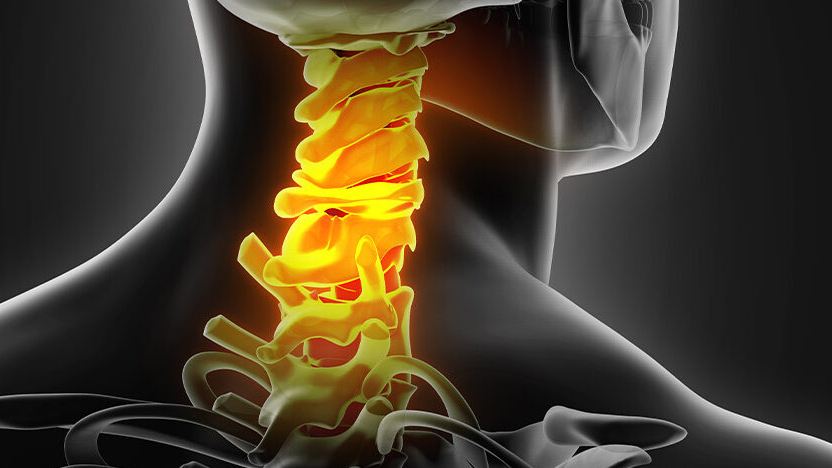

يمكن أن تكون تشنجات عضلات العنق مؤلمة للغاية وقد تتداخل مع

تدلي القرص العنقي، المعروف أيضًا باسم الانزلاق الغضروفي ، هو حالة

استئصال القرص العنقي الأمامي ودمج الفقرات العنقية (ACDF) هو إجراء جراحي